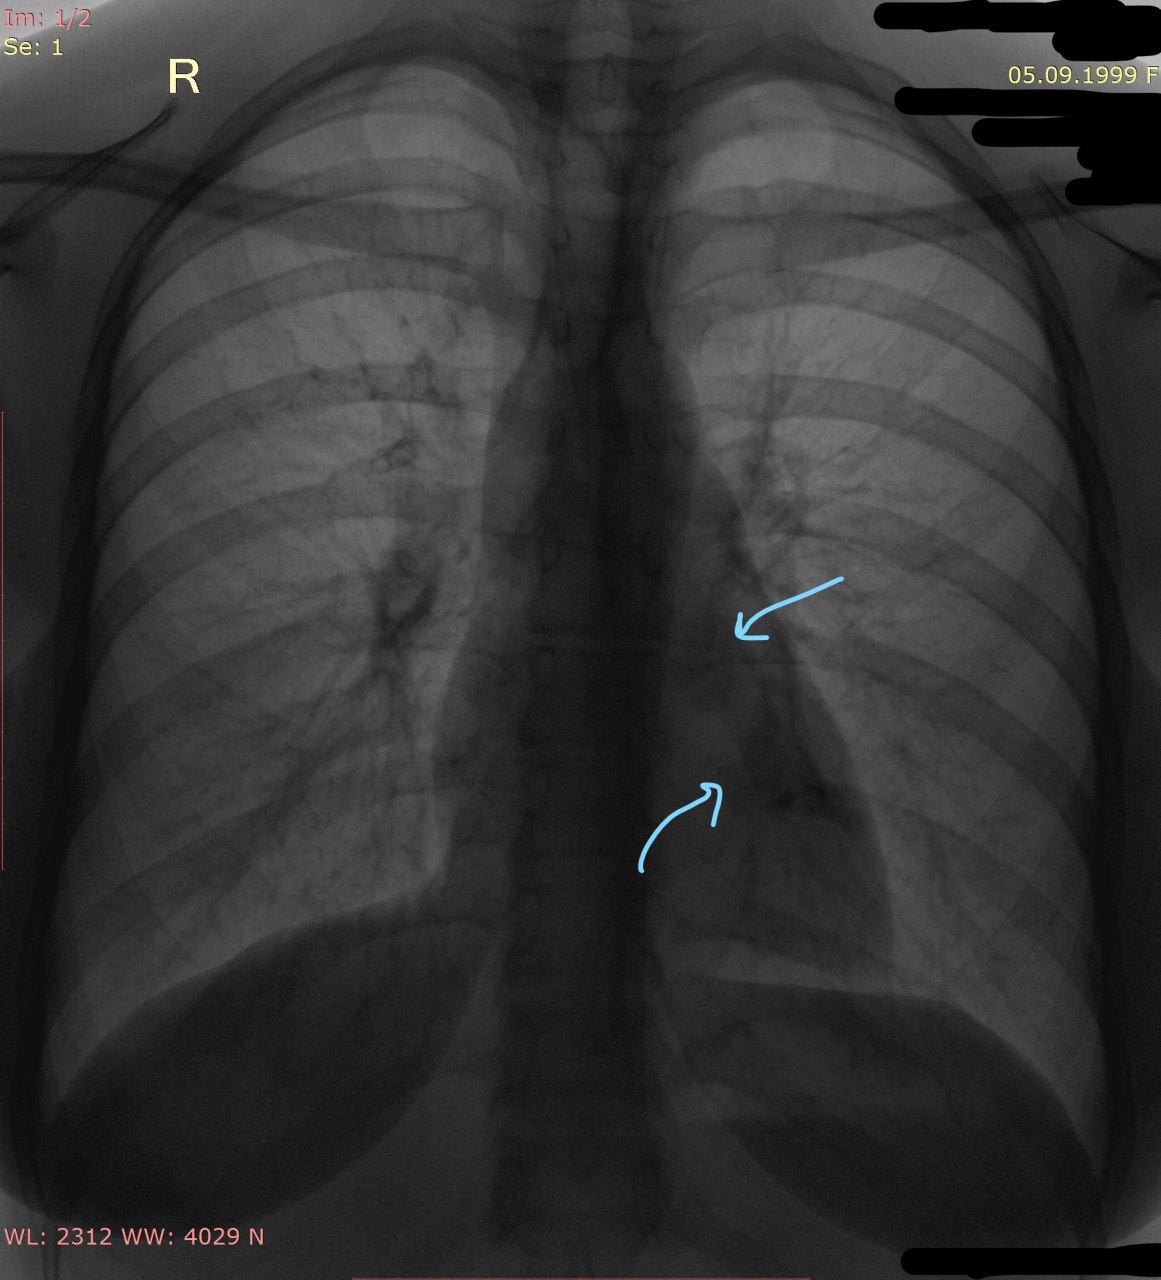

Щас жалобы упал на боли слева

Что с позвоночником? Слишком уж угол острый для сколиоза

Добрый день! Вчера поднялась температура до 39. Больше анамнеза нет

ВК

Смущают эти тени. Это суммация теней или инфильтрация все-таки?

ВМ

Суммарная